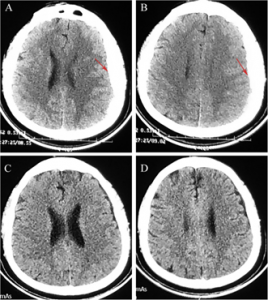

BEIJING, CHINA, May 9, 2025 /EINPresswire.com/ -- Patients with subacute subdural hematoma (sASDH) do not have an optimal non-surgical therapeutic strategy. In this study, scientists from Capital Medical University, Beijing, and Tianjin Medical University, Tianjin, present five case studies where patients received atorvastatin plus low-dose dexamethasone for sASDH. They report resolution of hematomas in all patients, with no recurrence or progression during the six-month follow-up period. This may be a potential alternative treatment for patients who prefer non-surgical therapy for sASDH.Acute subdural hematoma (ASDH) is a common brain lesion resulting from traumatic brain injuries and is associated with high mortality and morbidity. Emergency surgery is the most common intervention for these patients; however, in some cases, patients refuse to undergo surgery owing to social, religious, economic, or psychological reasons. In these cases, ASDH transitions to sASDH, and non-surgical interventions should begin immediately. However, there is no consensus in the medical community as to how to treat these patients non-surgically. To address this issue, researchers from Capital Medical University, Beijing, and Tianjin Medical University, Tianjin, China, set out to evaluate the efficacy of a combination of the drugs atorvastatin and dexamethasone in five patients who reported sASDH. This study was conducted under the guidance of Professor Rongcai Jiang and was published in the prestigious Chinese Neurosurgical Journal on April 2, 2025.

Previous phase-II randomized proof-of-concept trials had reported that atorvastatin plus low-dose dexamethasone was effective in patients with chronic SDH. Based on this, Prof. Jiang explains the rationale of their study “Considering that sASDH and chronic SDH share highly similar pathological and clinical characteristics, we speculate that atorvastatin combined with low-dose dexamethasone may be safe and effective for sASDH patients initially selecting nonsurgical therapy”. Of the five patients, four were females, aged between 30 and 85 years old. The male patient was a 97-year-old who presented with convulsions and atrial fibrillation. The medical histories of these patients were also varied, ranging from hemophilia to rectal and bladder cancers. Two female patients reported post-operative and post-fall SDH. All patients received 20 mg/day oral doses of atorvastatin along with a low-dose dexamethasone, where 2.25 mg/day was administered in the first 2 weeks, 1.5 mg/day in the third week, and 0.75 mg/day in the fourth week. After receiving this treatment regimen of atorvastatin plus low-dose dexamethasone treatment, patients’ symptoms improved significantly, with no cases of recurrence or progression of symptoms even up to 6 months post-treatment.

The lack of an optimal non-surgical treatment for sASDH prompted this study. The literature review suggests a high mortality rate of 7% which calls for an urgent non-surgical treatment plan for these patients. This study, although conducted in a small local pool of patients with sASDH, shows that atorvastatin with low-dose of dexamethasone successfully resolves symptoms and removes hematomas without recurrence during a six-month follow-up period.